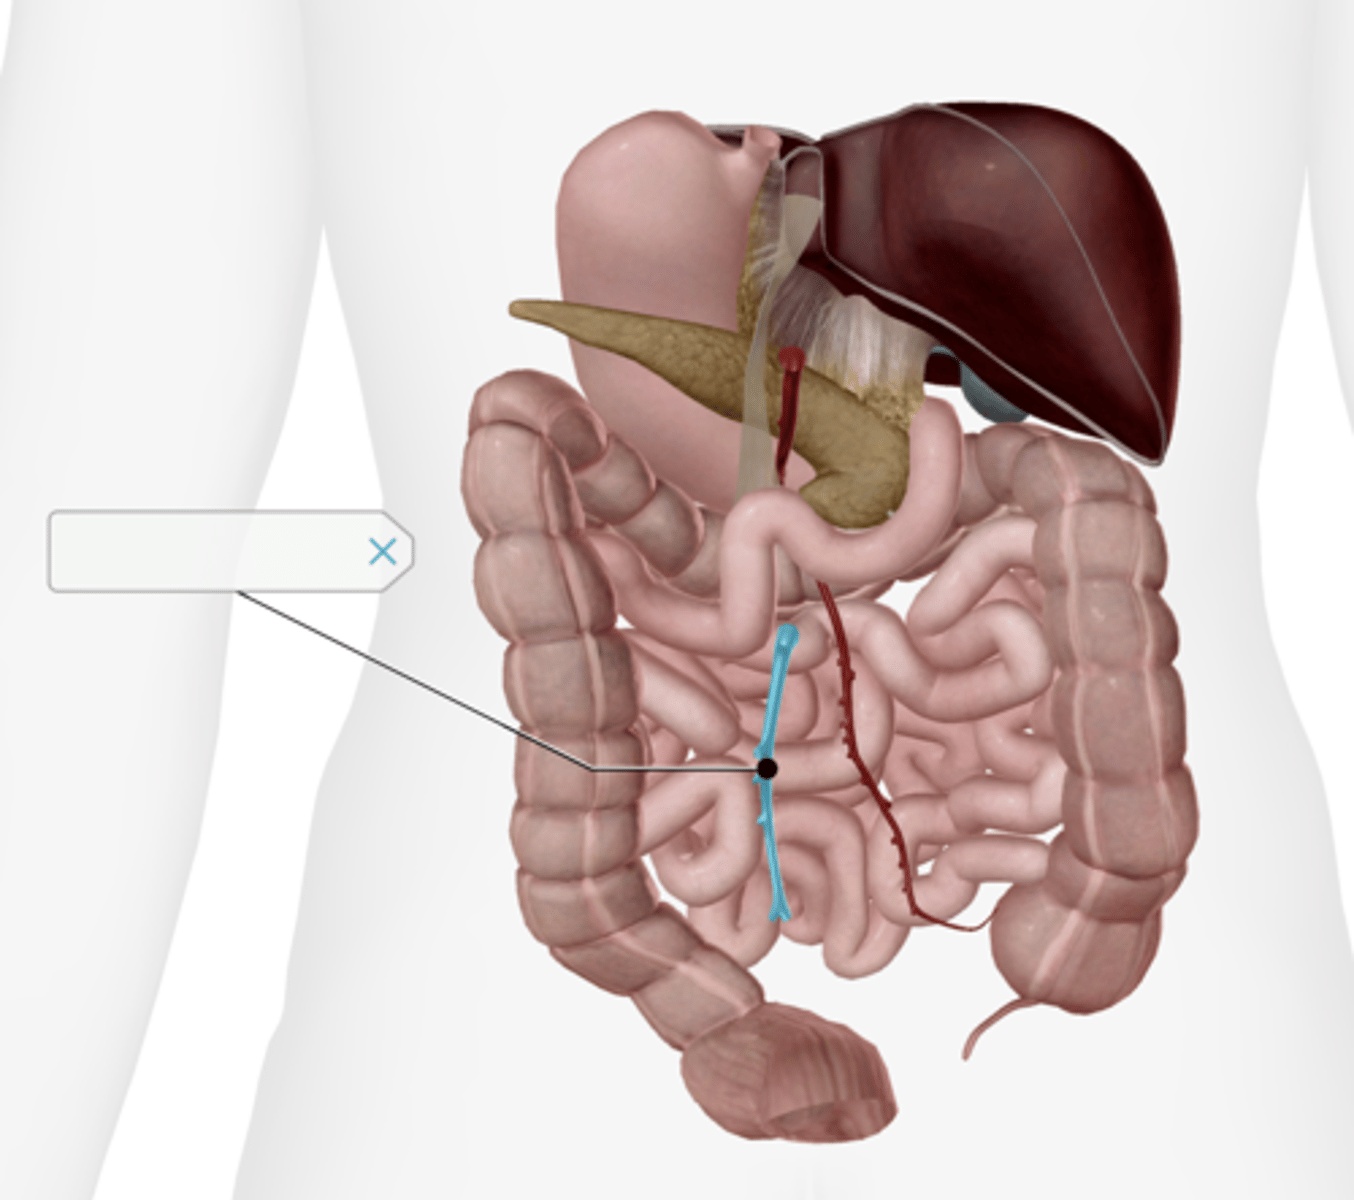

Jejunum

Ileum

Superior mesenteric artery

Inferior mesenteric artery